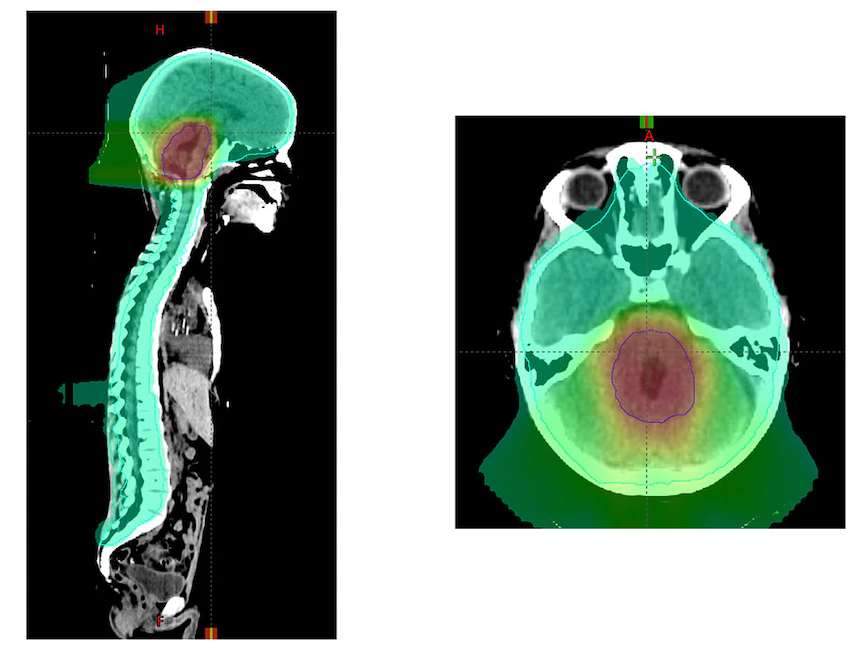

وفي الغالب، يتكون بروتوكول العلاج من جرعات من الإشعاع للدماغ والعمود الفقري بالكامل متبوعاً بجرعة إشعاعية إضافية إلى الجزء الخلفي من الدماغ تمنع هذا الانتشار، إلا إن الإشعاع المستخدم في علاج مثل هذه الأورام يؤثر سلباً على الدماغ، ويدمر الوظيفة الإدراكية، خاصة في المرضى الأصغر سناً الذين بدأت أدمغتهم للتو في التطور.

وأشارت الدراسة الأميركية الجديدة التي قادها علماء من كلية الطب بجامعة واشنطن في سانت لويس ومستشفى سانت جود لأبحاث الأطفال إلى أن الأطفال الذين يعانون من "الورم الأرومي النخاعي المتوسط الخطورة" يمكن أن يتلقوا "دفعة" إشعاعية مُسلطة على حجم أصغر من الدماغ في نهاية دورة علاج إشعاعي مدتها ستة أسابيع.

وقال الباحثون إن تلك الدفعة على منطقة أصغر لا تزال تحافظ على السيطرة نفسها على المرض مثل أولئك الذين يتلقون الإشعاع في منطقة أكبر لكن مع أعراض جانبية إدراكية أقل.

وفي تلك الدراسة، أراد الباحثون التحقيق فيما إذا كان بالإمكان تقليل كمية الإشعاع التي يتلقاها هؤلاء المرضى بأمان، مع تجنيب الأجزاء الطبيعية من الدماغ تلقي جرعات الإشعاع وتقليل الآثار الجانبية للأطفال المصابين بهذا النوع من سرطان الدماغ مع الحفاظ أيضاً على فعالية العلاج.

ووجد الباحثون أن تقليل جرعة الإشعاع المتلقاة على مدار 6 أسابيع من العلاج كان له تأثير سلبي على البقاء على قيد الحياة. ولكنهم وجدوا في الوقت ذاته أن يُمكن تقليل حجم المنطقة الدماغية التي تتلقى دفعة إشعاعية دون فقدان هدف العلاج، ودون أن يتسبب ذلك الأمر في انتشار الورم لمناطق أخرى.

ومن أجل تعزيز العلاج، تلقى جميع المرضى جرعة إشعاع تراكمية قدرها 54 جراي إما للمنطقة بأكملها من الدماغ المسماة "الحفرة الخلفية" والتي تشمل المخيخ أو إلى منطقة أصغر من الدماغ تتضمن المخطط الأصلي للورم بالإضافة إلى هامش إضافي يصل إلى حوالي 2 سم خارج حدود الورم الأصلية.

وأوضح الباحثون أن المرضى الذين عولجوا بدفعات إشعاع على منطقة ذات حجم أقل من الدماغ حصلوا تماماً على الفوائد العلاجية مثل أولئك الذين تلقوا دفعة الحفرة الخلفية بأكملها.

بالنسبة للمرضى الذين يتلقون علاجاً إشعاعياً على منطقة ذات حجم أصغر من الدماغ. فقد عاش 82.5% منهم لمدة خمس سنوات دون تفاقم السرطان.

وبالنسبة لأولئك الذين يتلقون حجماً أكبر من التعزيز للحفرة الخلفية بأكملها، نجا 80.5% منهم لمدة خمس سنوات دون تفاقم المرض. وهذا يعني أن المرضى الذين تلقوا إشعاعاً على منطقة دماغية ذات حجم أصغر تحسنت لديهم مستويات البقاء على قيد الحياة.